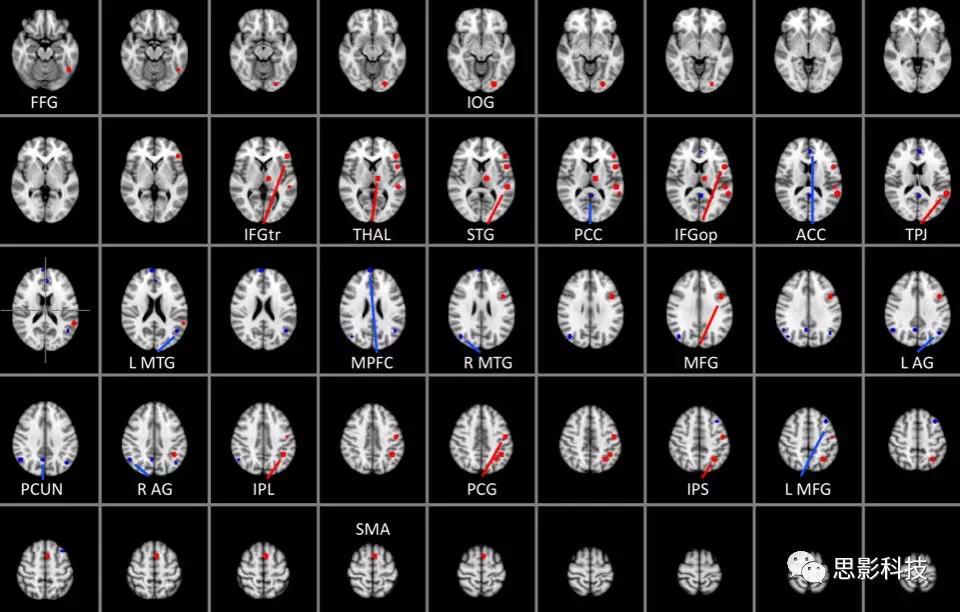

圖一 閱讀網(wǎng)絡(luò)種子點(diǎn)

S3. Reading Network(RN) 和 Default Mode Network (DMN)感興趣區(qū)的可視化. RN ROIs紅色標(biāo)記, DMN ROIs 藍(lán)色標(biāo)記.

縮寫詞: L = left, R = right; ACC = anterior cingulatecortex, AG = angular gyrus, FFG = fusiform gyrus, IFGop = inferior frontalgyrus pars opercularis, IFGtr = inferior frontal gyrus pars triangularis, IPL =inferior parietal lobule, IPS = intraparietal sulcus, IOG = inferior occipitalgyrus, MFG = middle frontal gyrus, MPFC = medial prefrontal cortex, MTG =middle temporal gyrus, PCC = posterior cingulate cortex, PCG = precentralgyrus, PCUN = precuneus, SMA = supplementary motor area, THAL = thalamus, TPJ =temporoparietal junction.